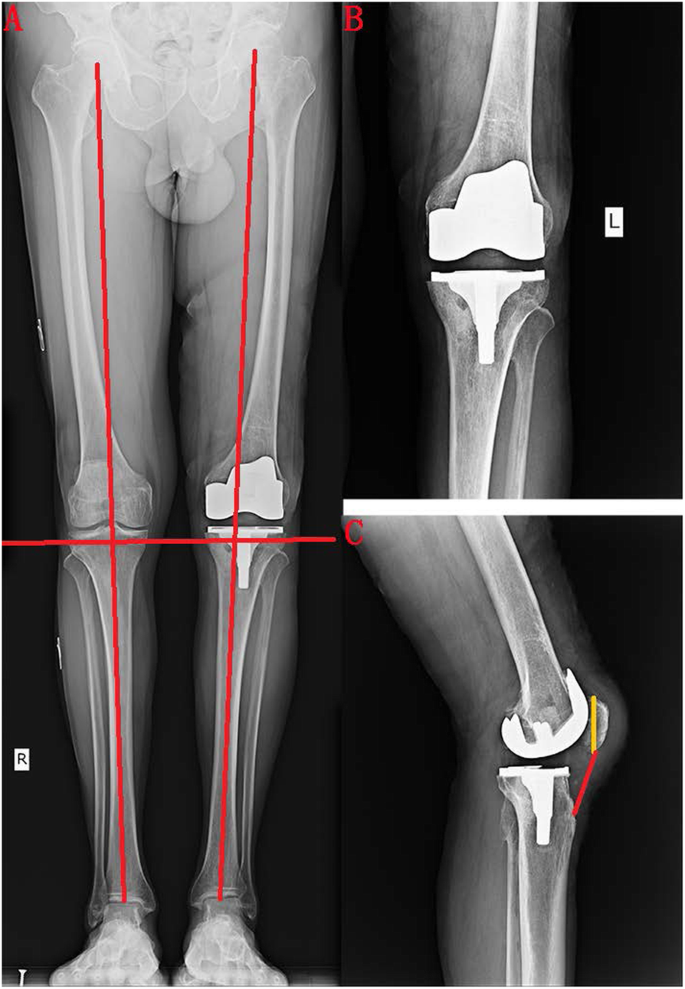

We are reporting a case of patellar tendon rupture from tibial tuberosity following total knee arthroplasty. A bunion also known as hallux valgus is a deformity of the joint connecting the big toe to the foot. Our long term result has been very encouraging.

National Center for Biotechnology Information. The hard outer layer of bones is composed of cortical bone which is also called compact bone as it is much denser than cancellous bone. We managed it by direct repair with fiberwire using Krackow suture technique without augmentation.

Our method is a safe. Boulette de genou en français cadien 1 chez lHomme est un petit os plat triangulaire situé à la partie antérieure du genou et articulé avec le fémurLa patella est un os sésamoïde 2. The patella also known as the kneecap is a flat rounded triangular bone which articulates with the femur thigh bone and covers and protects the anterior articular surface of the knee jointThe patella is found in many tetrapods such as mice cats birds and dogs but not in whales or most reptiles.